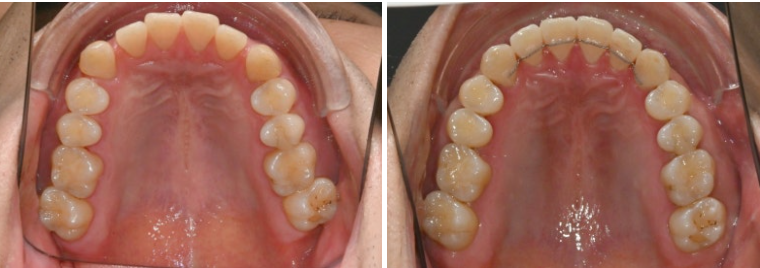

24.11

앞에서 보면 윗니가 아랫니를 많이 덮어서 앞니가 깊게 물리는 과개교합, 중심선 불일치,벌어진 앞니 등이 보입니다.

파란 화살표와 같이 물리는 상태를 가위교합이라고 합니다.

맨 뒤 큰 어금니에 흔하게 보이는 부정교합입니다.

위 어금니는 배열에서 바깥으로 나가있고

아래 어금니는 안으로 쓰러져 있습니다.

경미한 총생과 중심선 불일치, 가위교합, 벌어짐, 과개교합 문제가 있는 상황입니다.

24년 12월부터 25년 4월까지 라이트 프로그램에서 허용하는 장치 14개 모두 낀 후 모습입니다.

25.04